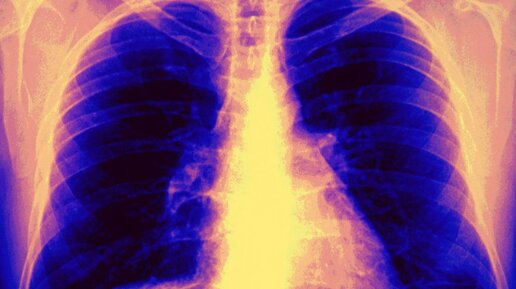

Как распознать легочное кровотечение

Легочное кровотечение – это нарушение, при котором из легких наружу выделяется кровь. Состояние может быть опасным, вплоть до смерти пациента. Поэтому необходимо очень быстро его распознать и немедленно обратиться за квалифицированной медицинской помощью. Какие признаки свидетельствуют про возникновение легочного кровотечения у человека? Через нос и рот Выделение крови из дыхательных путей при кровотечении может быть незначительным, в течение длительного времени либо резко манифестирующим, с выделением большого количества кровяных выделений...